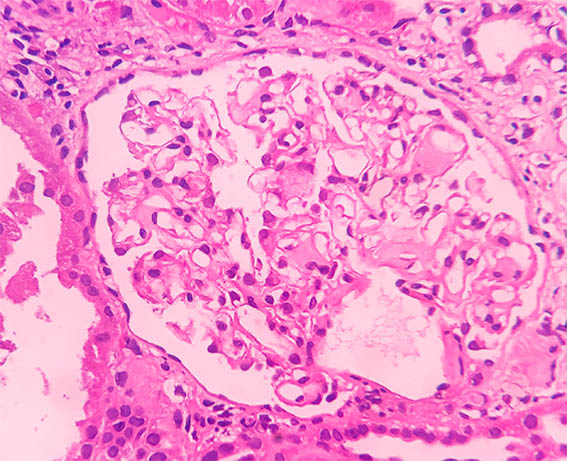

Figura 2. H&E, X200.

Figura 3.

H&E, X400.